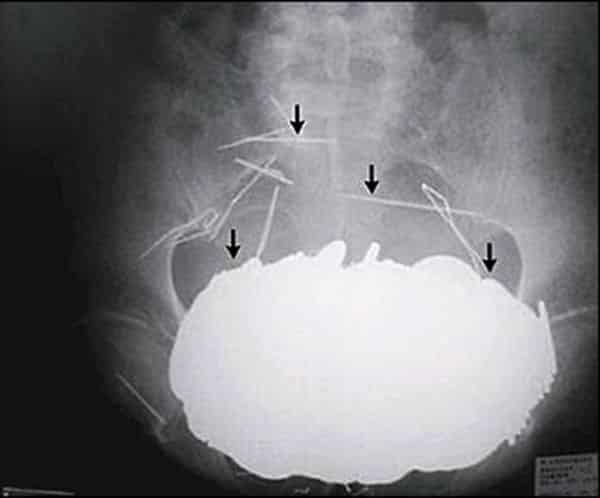

2. 78 couverts différents

Naître avec (plusieurs) cuillère en argent dans la bouche.